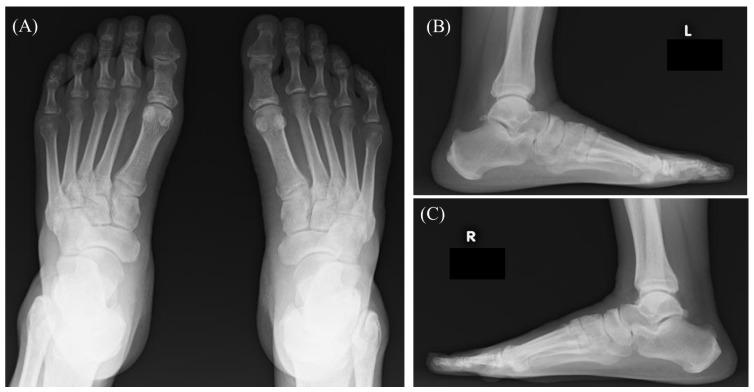

Chronic lymphocytic leukemia (CLL) is the most common leukemia in adults but is rare in Asia. Extramedullary and extranodal manifestations in CLL are generally uncommon, and muscle involvement is extremely rare. A 70-year-old male with CLL presented with bilateral plantar pain, predominantly on the left side. Anemia and reduced platelet count prompted ibrutinib treatment. MRI revealed high-signal areas in the muscles, suggesting inflammation. Anemia and thrombocytopenia improved, but the pain persisted for 8 months. Histopathological findings confirmed CLL infiltration of the muscles. Radiotherapy alleviated the pain, and the patient remains under observation. Careful caution was needed because (1) MRI findings suggested an inflammatory lesion, broadening differential diagnosis, and (2) CLL may coexist with inflammatory diseases. Histopathological examination is essential for correct diagnosis and treatment.

慢性淋巴细胞白血病(CLL)是成人中最常见的白血病,但在亚洲较为罕见。CLL的髓外和结外表现通常并不常见,肌肉受累极为罕见。一名70岁的CLL男性患者出现双侧足底疼痛,主要集中在左侧。贫血和血小板计数降低促使使用依鲁替尼进行治疗。MRI显示肌肉中有高信号区域,提示存在炎症。贫血和血小板减少症有所改善,但疼痛持续了8个月。组织病理学检查结果证实了CLL浸润肌肉。放疗缓解了疼痛,患者仍在接受观察。需要谨慎小心,原因如下:(1)MRI结果提示存在炎性病变,扩大了鉴别诊断范围;(2)CLL可能与炎性疾病并存。组织病理学检查对于正确诊断和治疗至关重要。